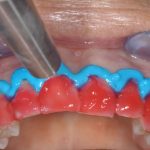

Sopravvivenza di Impianti Core-X® posizionati con chirurgia driver guidata

In questo articolo viene effettuata un’analisi retrospettiva per verificare la sopravvivenza di Impianti Core-X® posizionati con chirurgia driver guidata, con un follow up minimo...